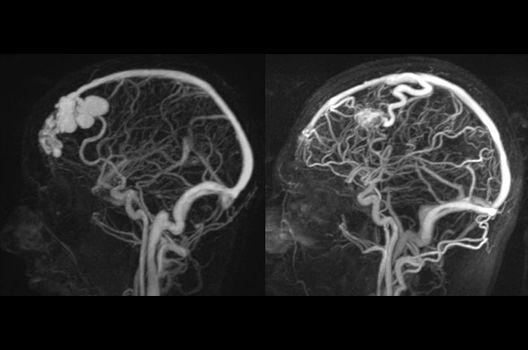

Die Magnetresonanztomographie (MRT) ist ein Verfahren, bei dem durch magnetische Kräfte Bilder des Körperinneren angefertigt werden. In der Neuroradiologie können manchmal kleinste Veränderungen schwere Folgen haben; daher forschen wir an der Entwicklung hochauflösender MRT-Sequenzen, mit denen diese Prozesse und auch einzelne Nervenfaserbahnen sichtbar gemacht werden können. Darüber hinaus sind bei vielen Erkrankungen des Gehirns die Blutgefäße betroffen. Daher arbeiten wir an der Neu- und Weiterentwicklung von MRT-Sequenzen zur Darstellung der Blutgefäße und zur Blutflussanalyse (sog. „Angio-MRT“). Einen besonderen Forschungsschwerpunkt unserer Klinik stellen die MR-Protonenspektroskopie und die funktionelle MRT dar, mit denen die Analyse einzelner chemischer Substanzen im Hirngewebe oder die Darstellung ausgewählter Hirnfunktionen möglich ist.

- Behandlung intrakranieller Gefäßmissbildungen